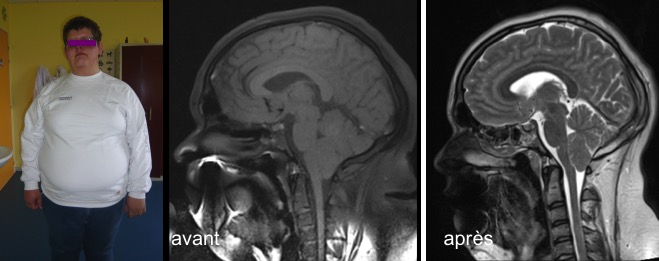

la malformation de Chiari isolée est une pathologie développementale, donc pas forcément congénitale, comme le montrent de rares cas de Chiari acquis documentés comme l’observation ci-dessous.

on observe parfois la constitution d’un engagement tonsillaire après un saignement méningé néonatal du à une souffrance périnatale (prématurité, anoxie, traumatisme néonatal). Statistiquement, la malformation de Chiari est plus souvent associé à une naissance difficile, un gros bébé, premier de fratrie (plus du tiers des cas dans notre expérience).